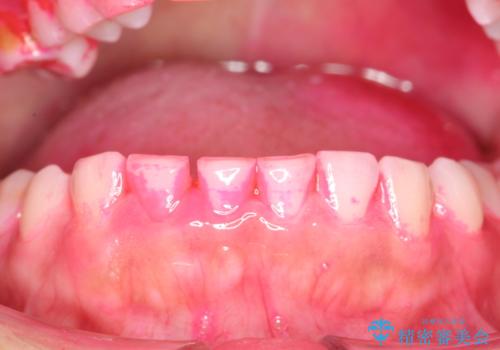

開始前

かなり久しぶりの歯科医院との事で、全体的に古くからの歯垢・歯石が多く付着していたため、自費クリーニング(PMTC)60分コース・歯周ポケット検査(保険適応)を行いました。